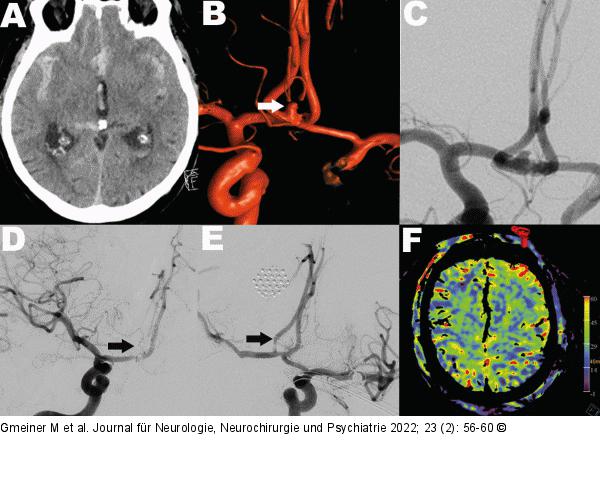

Abbildung 4: Hybrid-Eingriff Hybrid-Eingriff: A: Präoperatives Schädel-CT bei Subarachnoidalblutung. B: Die präoperative Angiographie zeigt ein rupturiertes Ramus communicans anterior Aneurysma (Pfeil). C: Ein Coilingversuch verlief frustran. D: Intraoperative Angiographie nach Clipping des Aneurysmas. Die rechte A. pericallosa ist verschlossen (Pfeil), bedingt durch eine dislozierte Gefäßplaque infolge des Clippings. E: Nach Durchführung der endovaskulären Dilatation des Gefäßes zeigt sich die A. pericallosa anhaltend rekanalisiert (Pfeil). F: In der intraoperativen Perfusionsmessung konnte ein seitensymmetrischer Blutfluss dargestellt und ein Territorialinfarkt ausgeschlossen werden. |

Hybrid-Eingriff: A: Präoperatives Schädel-CT bei Subarachnoidalblutung. B: Die präoperative Angiographie zeigt ein rupturiertes Ramus communicans anterior Aneurysma (Pfeil). C: Ein Coilingversuch verlief frustran. D: Intraoperative Angiographie nach Clipping des Aneurysmas. Die rechte A. pericallosa ist verschlossen (Pfeil), bedingt durch eine dislozierte Gefäßplaque infolge des Clippings. E: Nach Durchführung der endovaskulären Dilatation des Gefäßes zeigt sich die A. pericallosa anhaltend rekanalisiert (Pfeil). F: In der intraoperativen Perfusionsmessung konnte ein seitensymmetrischer Blutfluss dargestellt und ein Territorialinfarkt ausgeschlossen werden. |